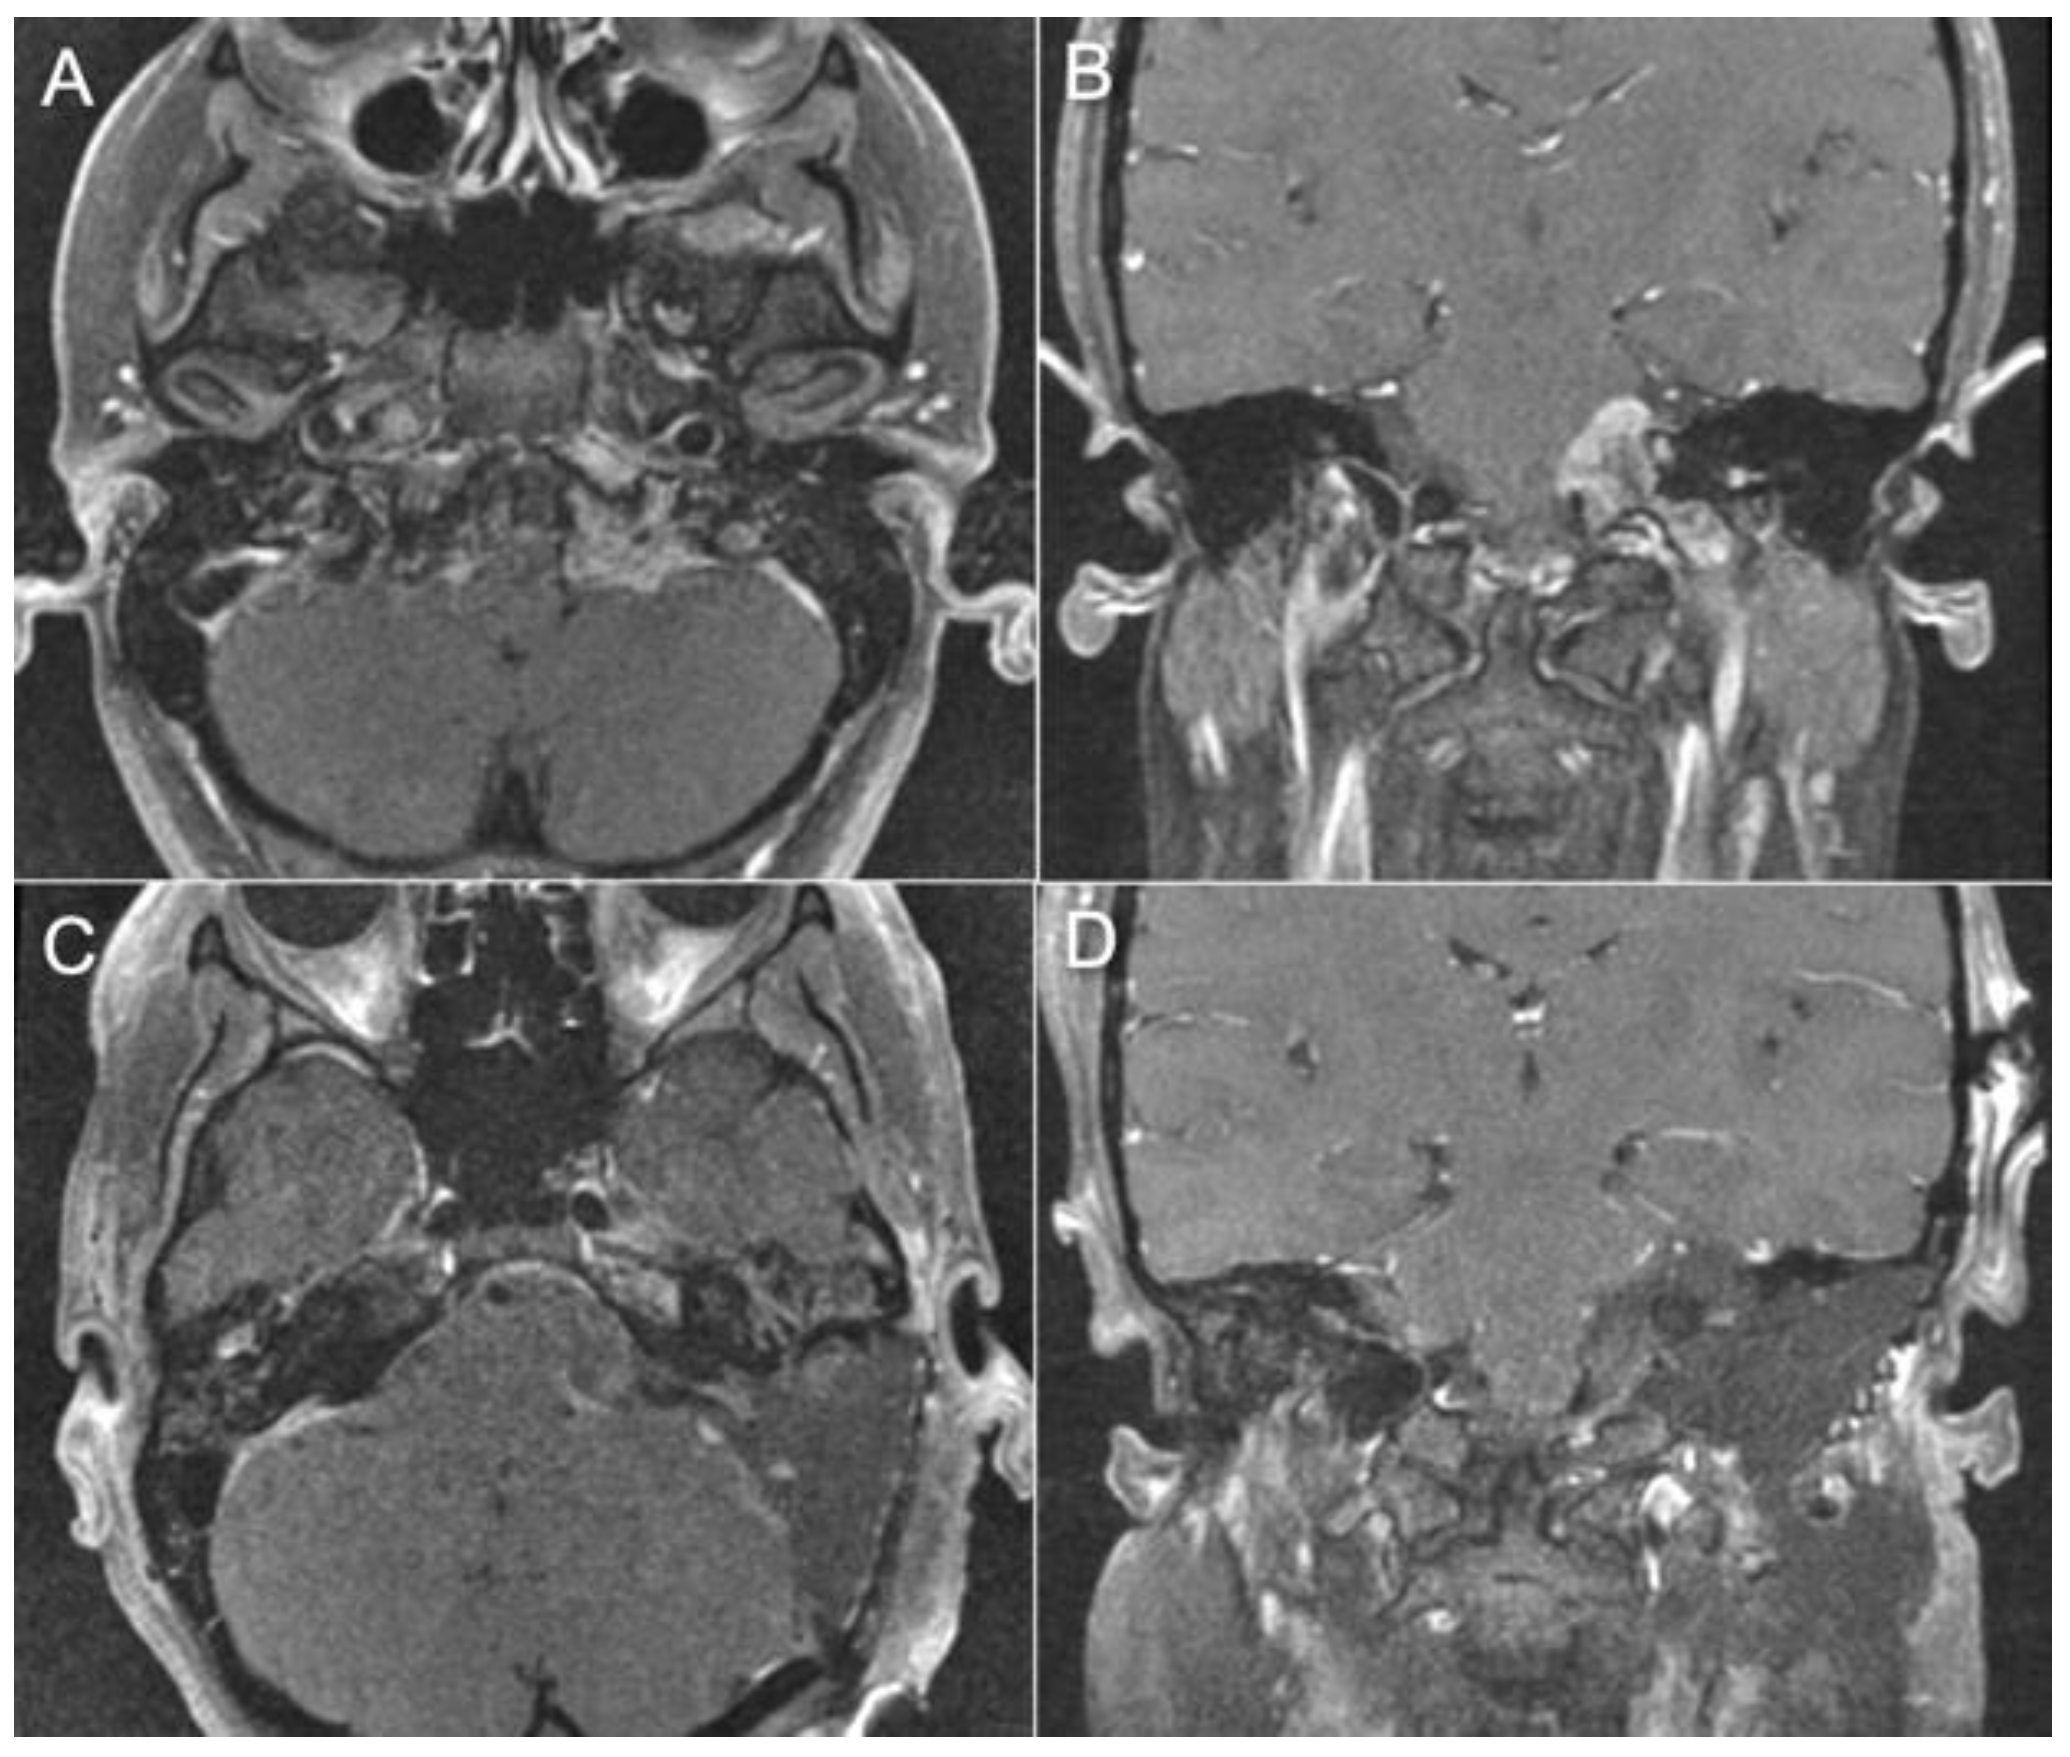

3.4. Representative Cases

- Case 1:

- Case 2:

- Case 3:

- Case 4: